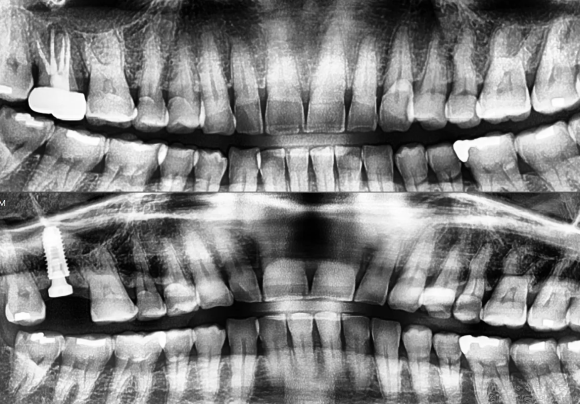

[숭실대입구역] [임플란트] 리더스진치과 2022.7.13 덴샤버를 이용한 무른 뼈의 발치 후 즉시 임플란트 식립과 상악동 거상술

​ 상악동 수술을 동반한 발치 후 즉시식립 케이스 입니다. ​ 덴샤버와 CAS KIT 그리고 기본 키트의 3중 이용하여 ​ 수술을 완료하고 ​ 3D 사진을 이용한 확인을 완료 하였습니다. ​ 단단한 뼈가 만들어져야 하기 때문에 ​ 5~6개월 후 상부 보철물을 올릴 예정입니다. ​ #상도동에서임플란트가장많이하는치과, #숭실...

상악동 수술을 동반한 발치 후 즉시식립 케이스 입니다.

덴샤버와 CAS KIT 그리고 기본 키트의 3중 이용하여

수술을 완료하고

3D 사진을 이용한 확인을 완료 하였습니다.

단단한 뼈가 만들어져야 하기 때문에

5~6개월 후 상부 보철물을 올릴 예정입니다.